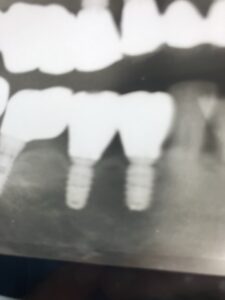

インプラントの上部構造の最終補綴物にメタルボンドと呼ばれるセラミックが使用されていました。今でも使用しますが1番の欠点として破折の可能性があることです。近年、物性や神秘性が格段に向上したジルコニアが、第一選択上がるようになりました。

フルジルコニアクラウンは、歯科補綴の一種で、全てジルコニアというセラミック素材でできた被せ物(クラウン)のことです。従来の金属にセラミックを焼き付けたメタルボンドクラウンとは異なり、アレルギーの原因となりうる金属は使用しません。

- 優れた生体親和性: 金属アレルギーの心配がなく、歯茎との親和性も高いため、歯周組織に優しいとされています。

- プラークが付着しにくい: 表面が滑らかなため、 歯石やプラークが付着しにくく、 インプラント周囲炎のリスクを低減する可能性があります。